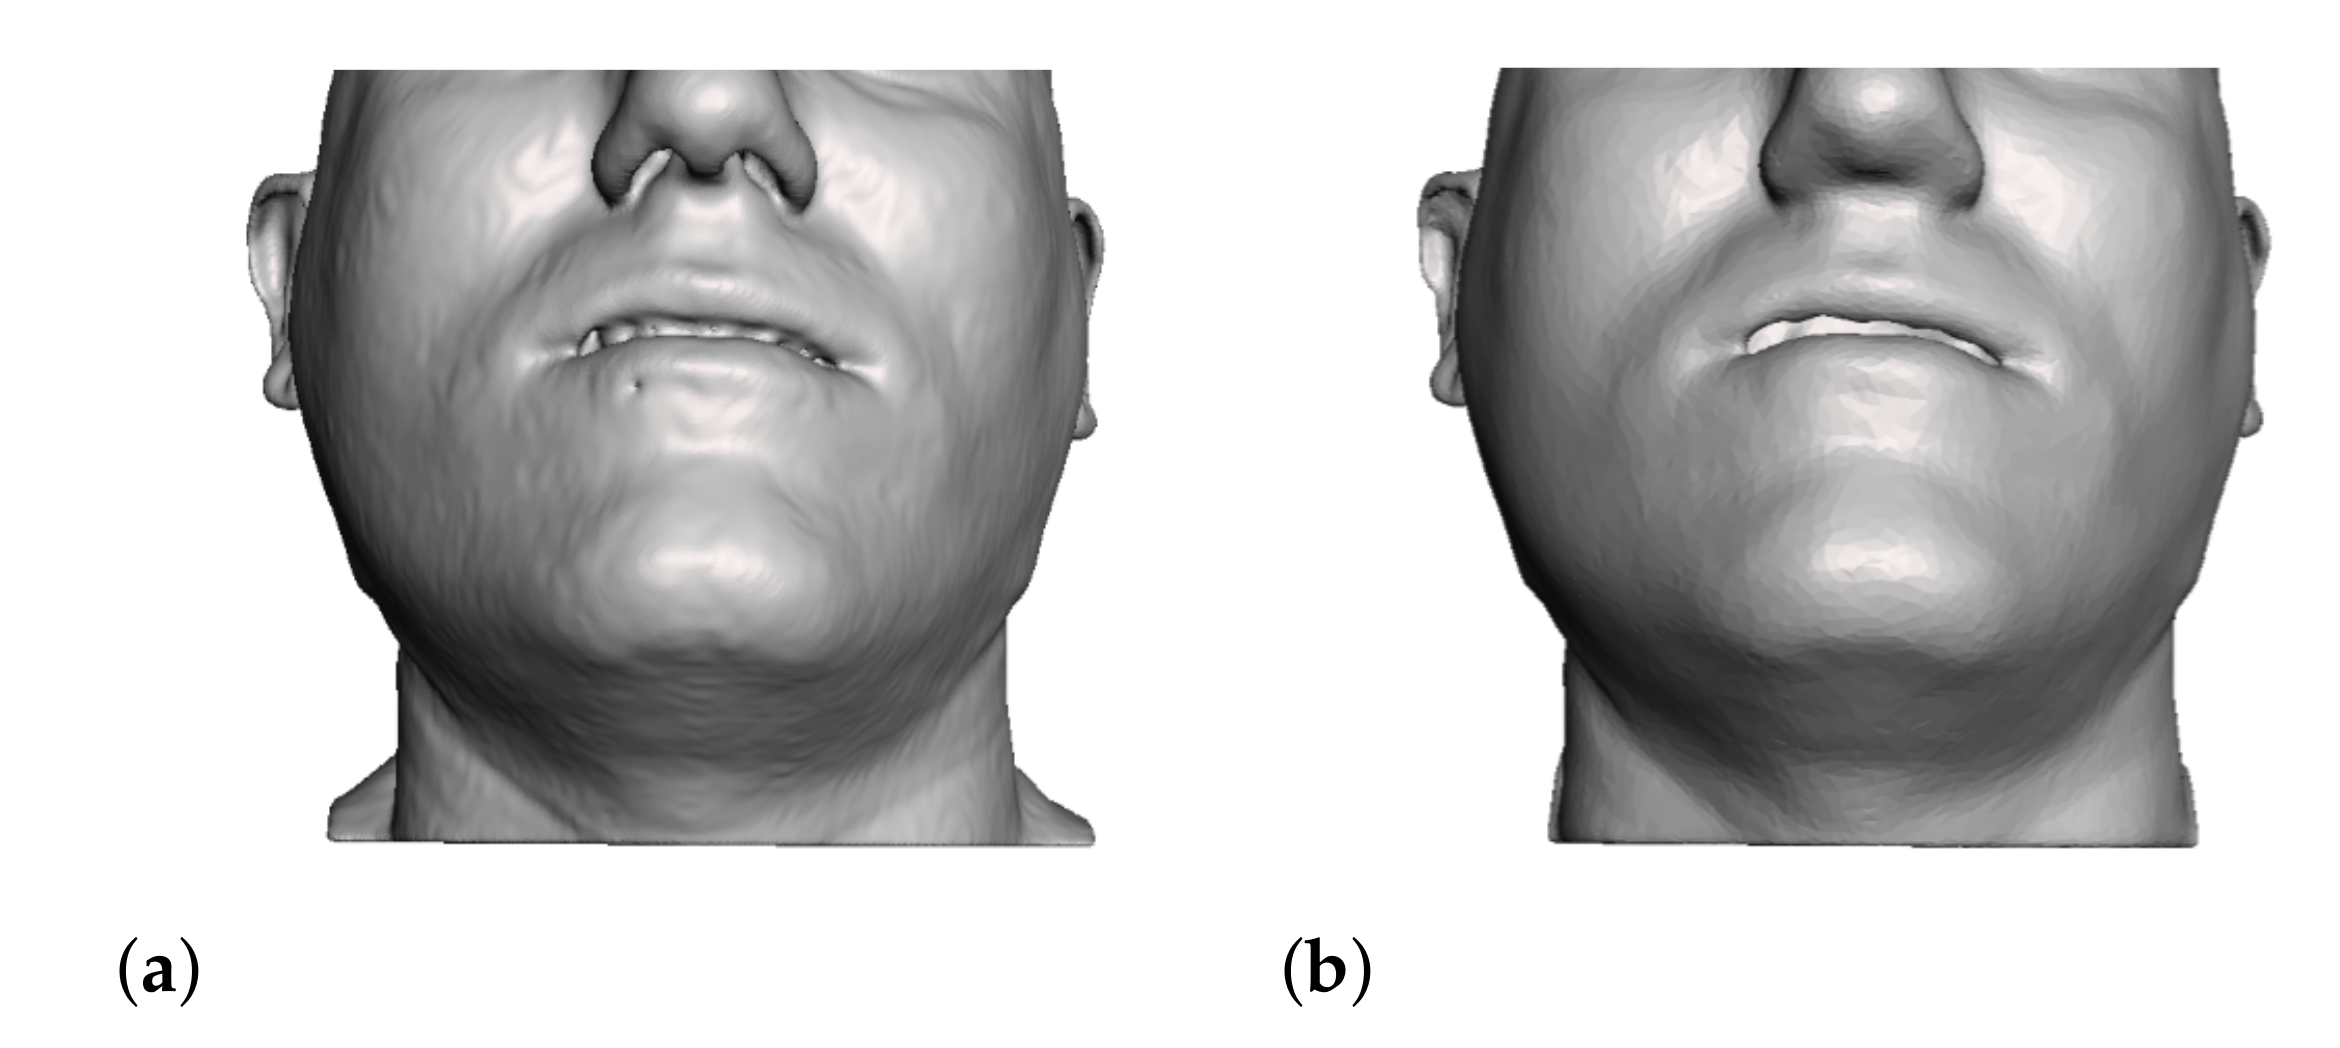

- Segmentation of the maxilla and mandible. For all patients, the highest error (except for the neck, which is not clinically relevant as discussed above) appears near the cut areas, both of the maxilla (e.g., patients M5 and M7) and the mandible (e.g., patients M1 and M3). This is probably due to the presence of fixation plates and/or bone grafts in the real result (e.g., patient M10, whose maxilla was not segmented, but where the presence of bone graft has been confirmed by the surgeon who carried out the intervention). As a consequence, patients with a segmented maxilla and/or mandible show in general larger error than those without segmented bones. However, the smooth coupling method proposed in Section 2.3.3 reduces considerably the error in cut areas, as shown in Figure 2.

4.3. Comparison of Fine and Coarse Meshes